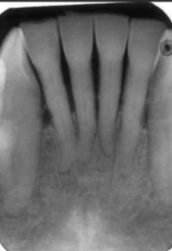

normal alveolar bone

first sign of bone loss is loss of cortication of interproximal bone

Alveolar crest

The highest point of alveolar bone that supports the teeth, should be between 0.5 - 2 mm from the CEJ.

used to view anterior crestal bone

normal PA, can take BW but not common